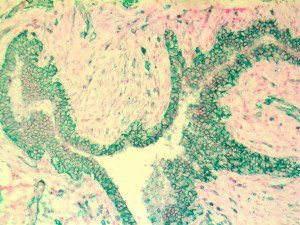

Clinical and laboratory manifestations of HLH include fever, enlarged liver and/or spleen, neurologic dysfunction, coagulopathy, liver dysfunction, cytopenias (i.e., low levels of erythrocytes, leukocytes, and/or platelets), hypertriglyceridemia, hyperferritinemia, hemophagocytosis, and eventually diminished NK cell activity as the immune system becomes progressively paralyzed. HLH can be familial (primary HLH) or secondary to another disease process (sHLH), such as rheumatic disease, in which it is referred to as macrophage activation syndrome (MAS, characterized by elevated ferritin).

This activation induces inflammatory monocytes to highly express IL-6, starting a localized and then systemic cascade effect that results in hyperproduction of IL-6, which accelerates the inflammatory process. Because IL-6 also increases vascular permeability, excessive levels cause blood vessels to become very leaky. This, along with clotting factors released from vascular endothelial cells, stimulates the coagulation cascade, resulting in microthrombosis (tiny clots), which leads to ischemia and tissue death of the kidney, intestines, heart, liver, brain and extremities.